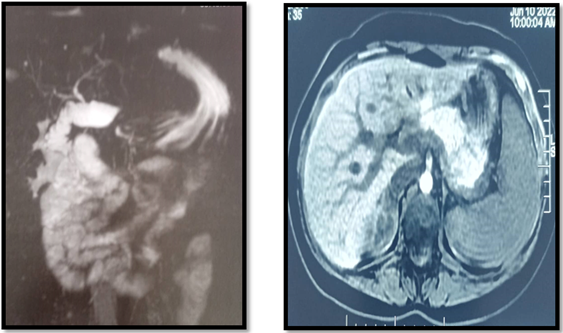

Our 30-year-old patient presented with nausea and abdominal pain in the right hypochondrium. Physical examination showed no mucocutaneous jaundice or pallor with slight tenderness of the right hypochondrium. Laboratory tests, including liver function tests, showed a slight elevation of YGT and PAL. Abdominal ultrasonography showed a sclero-atrophic gallbladder, with fine intra- and extra-hepatic bile ducts and a thin duct of Wirsung. The ultrasound appearance and cholestasis justified a Bili MRI (Figure 1) concluding to a homogeneous liver with regular contours and no detectable focal lesions ,the vesicular loge was free in relation to agenesis, the bile ducts were not dilated, the pancreas was normal in appearance with a fine Wirsung.

Figure 1 MRI photo showing missing gallbladder.

An abdominal CT scan revealed no ectopic location of the gallbladder; the diagnosis was agenesis of the gallbladder; the pain improved with antispasmodic medication.